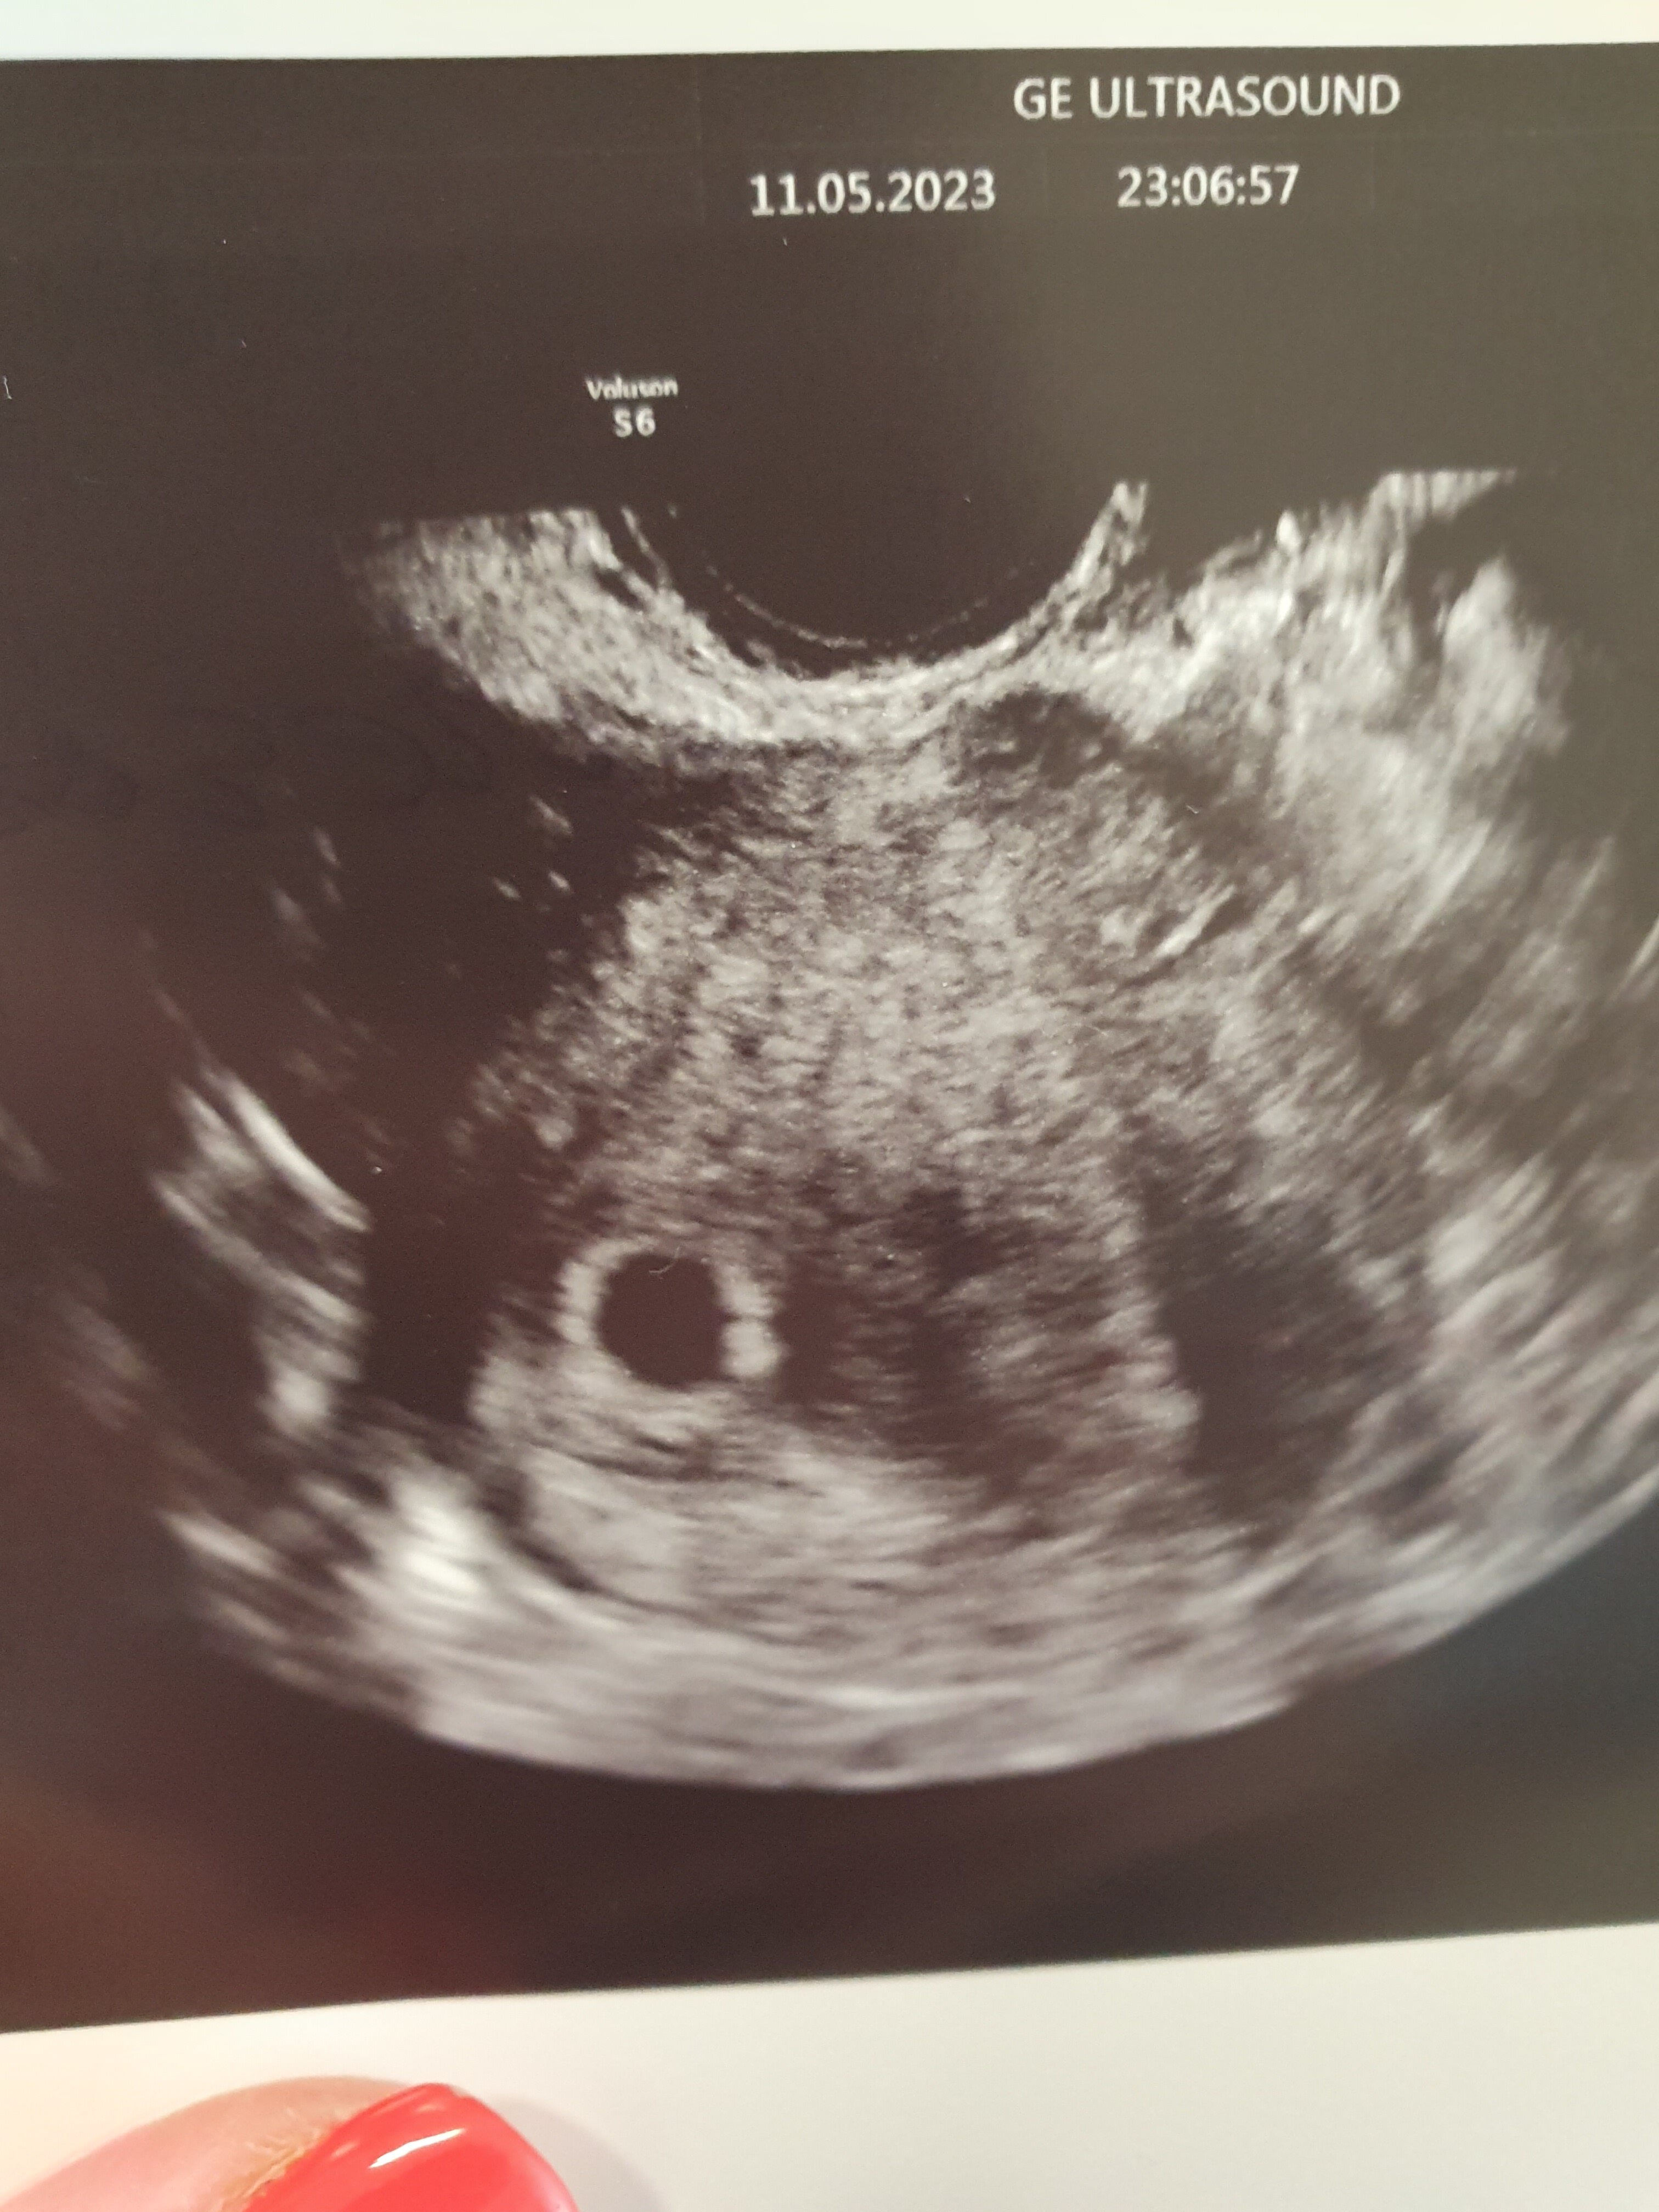

ulalala .. rzeczywiście beta ładnie skoczyła, prog też ruszył w góręJa dziś zbadałam zbadałam przyrost bety i progesteron

9.05 beta 64,5 prog 16,4

11.05 beta 203,5 prog 17,01 coś tam urósł, ważne, że nie spadłchyba na razie póki nic mi nie dolega odpuszczę badanie i poczekam do wizyty, nie będę się już niczym stresować

Dobrze to wygląda